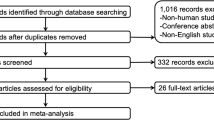

To investigate the brain functional abnormality of hyperthyroid patients before and after treatment for one month using resting-state functional magnetic resonance imaging (rs-fMRI). Amplitude of low-frequency fluctuation (ALFF) and seed-based functional connectivity (FC) analysis were performed in 27 new-onset untreated hyperthyroid patients relative to 30 healthy controls. In addition, follow-up data were available for 19 patients treated with methimazole for one month. Compared with healthy controls, patients exhibited lower ALFF in the right posterior cingulate cortex (PCC); increased FC in the bilateral anterior insula (AI), bilateral posterior insula (PI) and left anterior lobe of the cerebellum (ALC); and decreased FC in the bilateral lateral prefrontal cortex (LPFC), the right medial temporal gyrus (MTG) and the bilateral PCC. Compared with the hyperthyroid status, patients with improved thyroid function showed increased FC in the right LPFC and right dorsolateral prefrontal cortex (DLPFC). Subsequently, Pearson’s correlation analyses were performed between abnormal ALFF, FC, neuropsychological assessment and serum free triiodothyronine (FT3) levels. The results indicated that the alterations in regional and network-level brain functions, which might underlie different psychiatric complications were dynamic and interactional processes in hyperthyroidism. Moreover, the improvement in regional brain FC was correlated with the efficacy of anti-thyroid medication.

Subjects

The study was approved by the local Medical Research Ethics Committee of Xinqiao Hospital(Chong Qing, China), and the study was conducted in accordance with the approved guidelines and regulations. All participants provided their written informed consent after receiving a detailed description of the study procedures and aims. The experimental group recruited 27 right-handed patients (15 females and 12 males, age range: 18–50 years, mean age: 30.59 ± 7.87 years) with newly diagnosed and untreated Graves’ hyperthyroidism from the Endocrinology Department of XinQiao Hospital. All patients had elevated FT3 and FT4 and depressed TSH. The onset of clinical symptoms, including neuroticism, erethism, tremor, bulimia, easy fatigability and rapid emaciation, was recorded to determine the duration of hyperthyroidism. One month after anti-thyroid treatment, only 19 patients with hyperthyroidism were recalled to undergo the second comprehensive assessment. The control group consisted of 30 healthy right-handed volunteers(18 females and 12 males, age range: 18–50 years, mean age: 30.46 ± 4.4 years) who were recruited by networking in the local community. The same tests of thyroid function were administered to the control subjects, and all TH levels were within normal ranges (FT3 = 3.1–6.89 pmol/l, FT4 = 11.0–22.0 pmol/l, TSH = 0.27–4.2 mIU/ml).

The following exclusion criteria were applied to all subjects: a history of head injury, psychiatric disorders, alcohol or drug abuse, serious physical illness and contraindications to MR scanning. Two experienced neuroradiologists inspected the T 1 MR images to exclude gross neuroanatomic abnormalities. The final study groups contained 27 hyperthyroid patients before and 19 patients after receiving methimazole therapy as well as 30 healthy controls. The healthy control group was well matched with the untreated hyperthyroidism group according to sex, age and years of education.

Differences in demographic and clinical data between the 27 patients and 30 healthy controls were tested using a two-sample t-test with SPSS 20.0 for Windows(SPSS, Chicago, IL, USA). The Chi-square test was used to detect differences in sex. Next, the paired-samples t-test was used to evaluate the effects of anti-thyroid therapy on clinical data in the group of 19 patients. Significance was set at p < 0.05.

ALFF and FC map analyses were performed with SPM8 software (http://www.fil.ion.ucl.ac.uk/spm/). To characterize the pretherapeutic differences in ALFF and FC in the 27 hyperthyroid patients compared with the 30 normal subjects, a two-sample t-test was performed voxel-by-voxel after controlling for several covariates, including age, sex, mean value of head motion and years of education. Then, a paired-samples t-test was used to assess the possible changes in ALFF and FC after the administration of methimazole for one month in the group of 19 patients. Head motion was used as a covariate. For all of the above analyses, significance in the resulting statistical maps was set at 0.001, and a gray matter (GM) group mask was involved in the ALFF and FC calculations. The correction of results for multiple comparisons was divided into two parts: initially, to precisely define the peak points of brain regions with abnormal local brain activity in hyperthyroid patients as the seed regions for further FC analysis. The result maps of ALFF were corrected with the AlphaSim program (individual voxel p-value = 0.001, GM group mask, iteration = 1000) in DPABI software. The statistical threshold for pre-therapy ALFF was set at p = 0.001 and cluster size >35 voxels. Subsequently, the primary results of FC were displayed as statistical parametric maps (SPMs) in a standard MNI space at an initial threshold probability of p = 0.001 (uncorrected for multiple comparisons) and a cluster size threshold of 15 contiguous voxels. To fully explore the possible changes in brain connectivity before and after anti-thyroid therapy, statistical inference was performed in two steps with regard to the results of whole-brain FC calculations. First, a relatively strict statistical threshold of p = 0.001 in AlphaSim corrected for multiple comparisons was applied to the whole brain. The statistical threshold for FC was set at p = 0.001 and cluster size >68 voxels in pre-therapy and cluster size >44 voxels in post-treatment. Second, based on the results reported in previous studies10,11,12,13,14,15, 29 for the posterior cingulate cortex, frontal cortex, anterior cingulate cortex, temporal gyrus, cerebellum, insula and hippocampus, we used small volume-corrected (SVC) over these brain regions predicted a priori to demonstrate abnormalities in hyperthyroidism. These flexible statistical analyses were conducted using a family-wise error(FWE)-corrected threshold of p < 0.05 over the volume of the SVC-based hypothetical region, with a cluster size threshold of 15 contiguous voxels. Compared with a stricter correction for the whole brain, the SVC method enables hypothesis-driven analyses to be conducted with correction for multiple comparisons particularly in the cerebral region of interest43, 44.